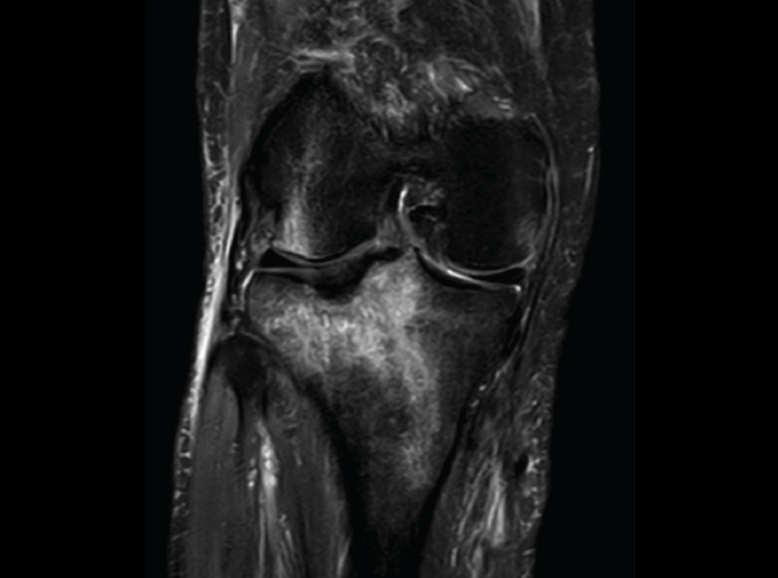

2. Fracturas

Se observa una hiposeñal de la médula ósea en secuencias T1 e hiperseñal en STIR o saturación grasa T2.

2.1. Edema óseo y fractura subcondral (Figura 47)

Figura 47. Corte de secuencia coronal T2 Fat-Sat de RM de rodilla: zona de edema óseo en la meseta tibial externa por contusión.

2.2. Fractura reciente (Figura 48)

Figura 48. Corte de secuencia coronal T2 Fat-Sat de resonancia magnética de rodilla: edema de médula ósea en la meseta tibial externa que ayuda al diagnóstico de fractura reciente en caso de duda.